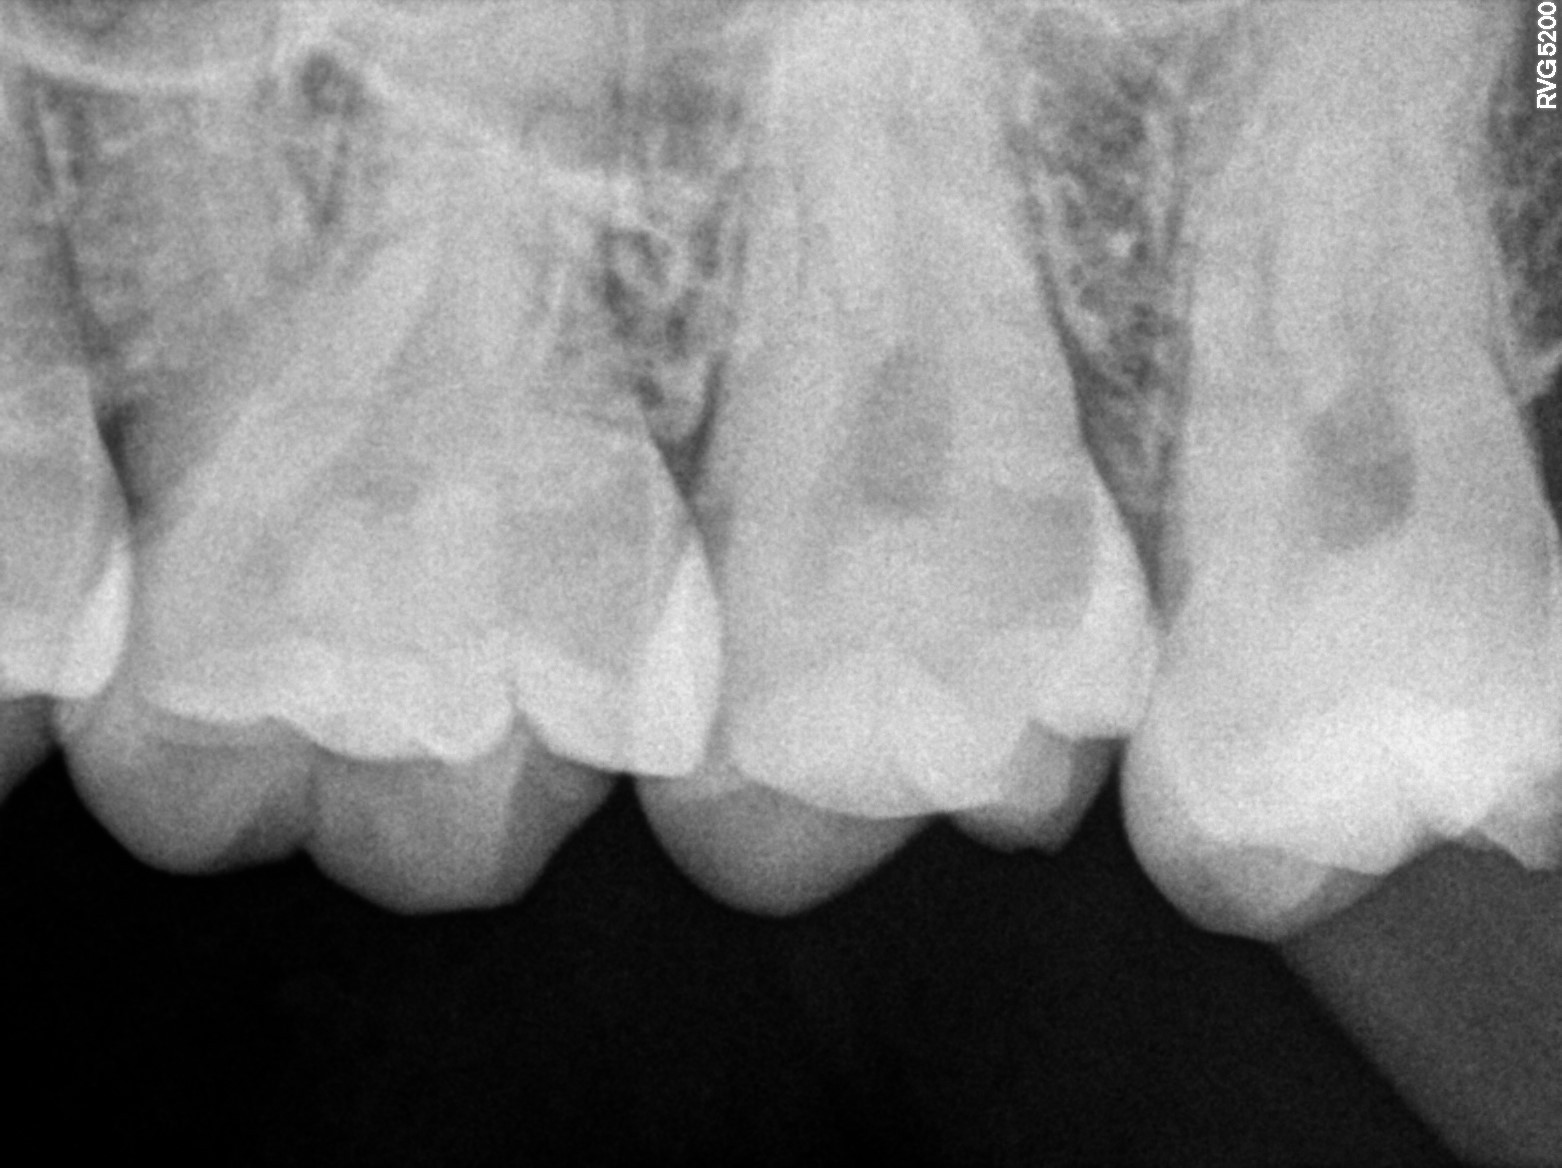

Dental Radiographs FHIR: DocumentReference · LOINC 24641-7

xray_1766483090_0.jpg

24641-7